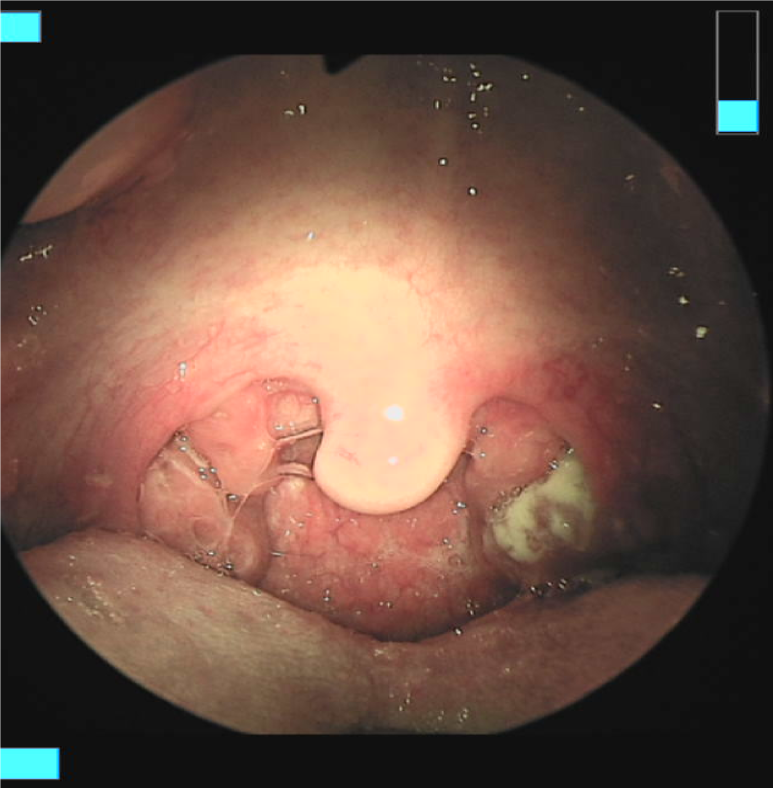

편도 주위 농양으로 진행되어 옛 인도 내경이 좁아져 기도가 막힐 위험이 있다.경구 항생제로 호전되지 않고 편도 주위 농양으로 진행되며, 기도 폐쇄의 위험이 있거나 탈수 증상을 보여 집에서 보호받을 수 없는 경우에는 입원 치료를 고려합니다.